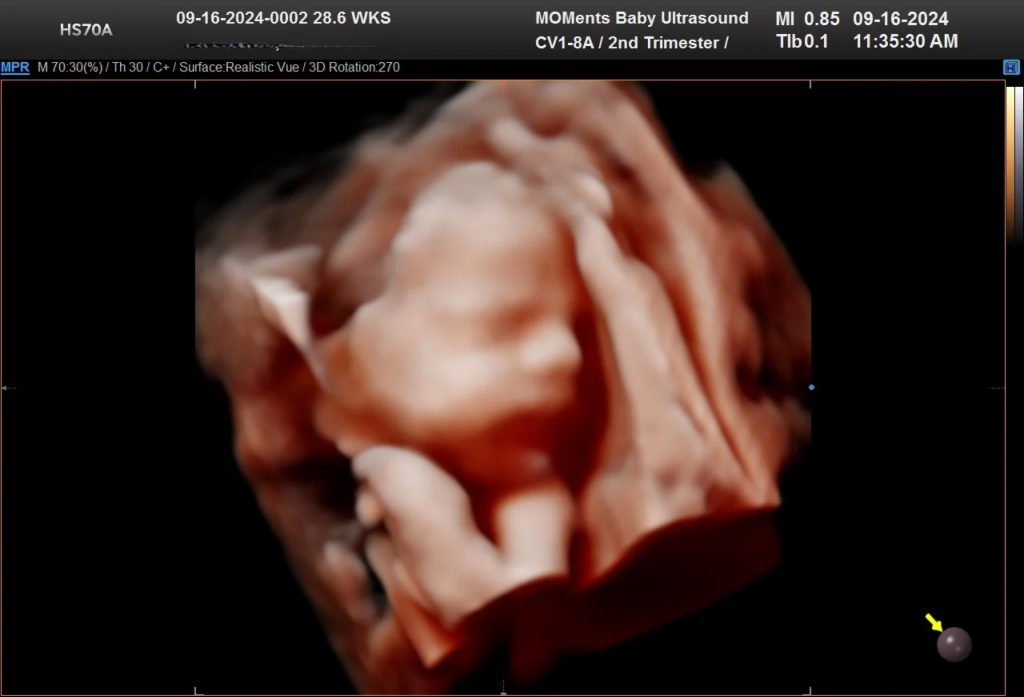

Ultrasound 4D menambah elemen masa, memperlihatkan pergerakan janin secara langsung.

Ultrasound 5D pula menawarkan pengalaman yang lebih nyata dengan kualiti gambar yang lebih terperinci, membantu doktor dan ibu bapa melihat perkembangan janin dengan lebih jelas.